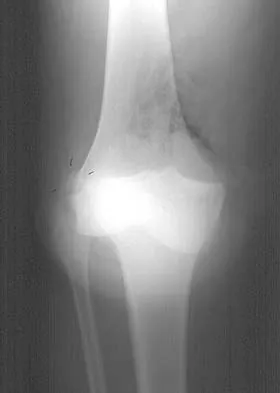

A 45-year-old male karate instructor sustained the injury shown in Figures 40a through 40c while practicing karate. The decision to proceed with surgery depends on which of the following factors?

The most important criteria in determining the need for surgery following a nondisplaced or minimally displaced tibial plateau fracture is knee stability to varus/valgus stress. Soft-tissue injury noted on MRI may be addressed at a later time following fracture healing. This fracture pattern is amenable to nonsurgical management. Decisions regarding surgical intervention may be made up to 2 weeks after injury.